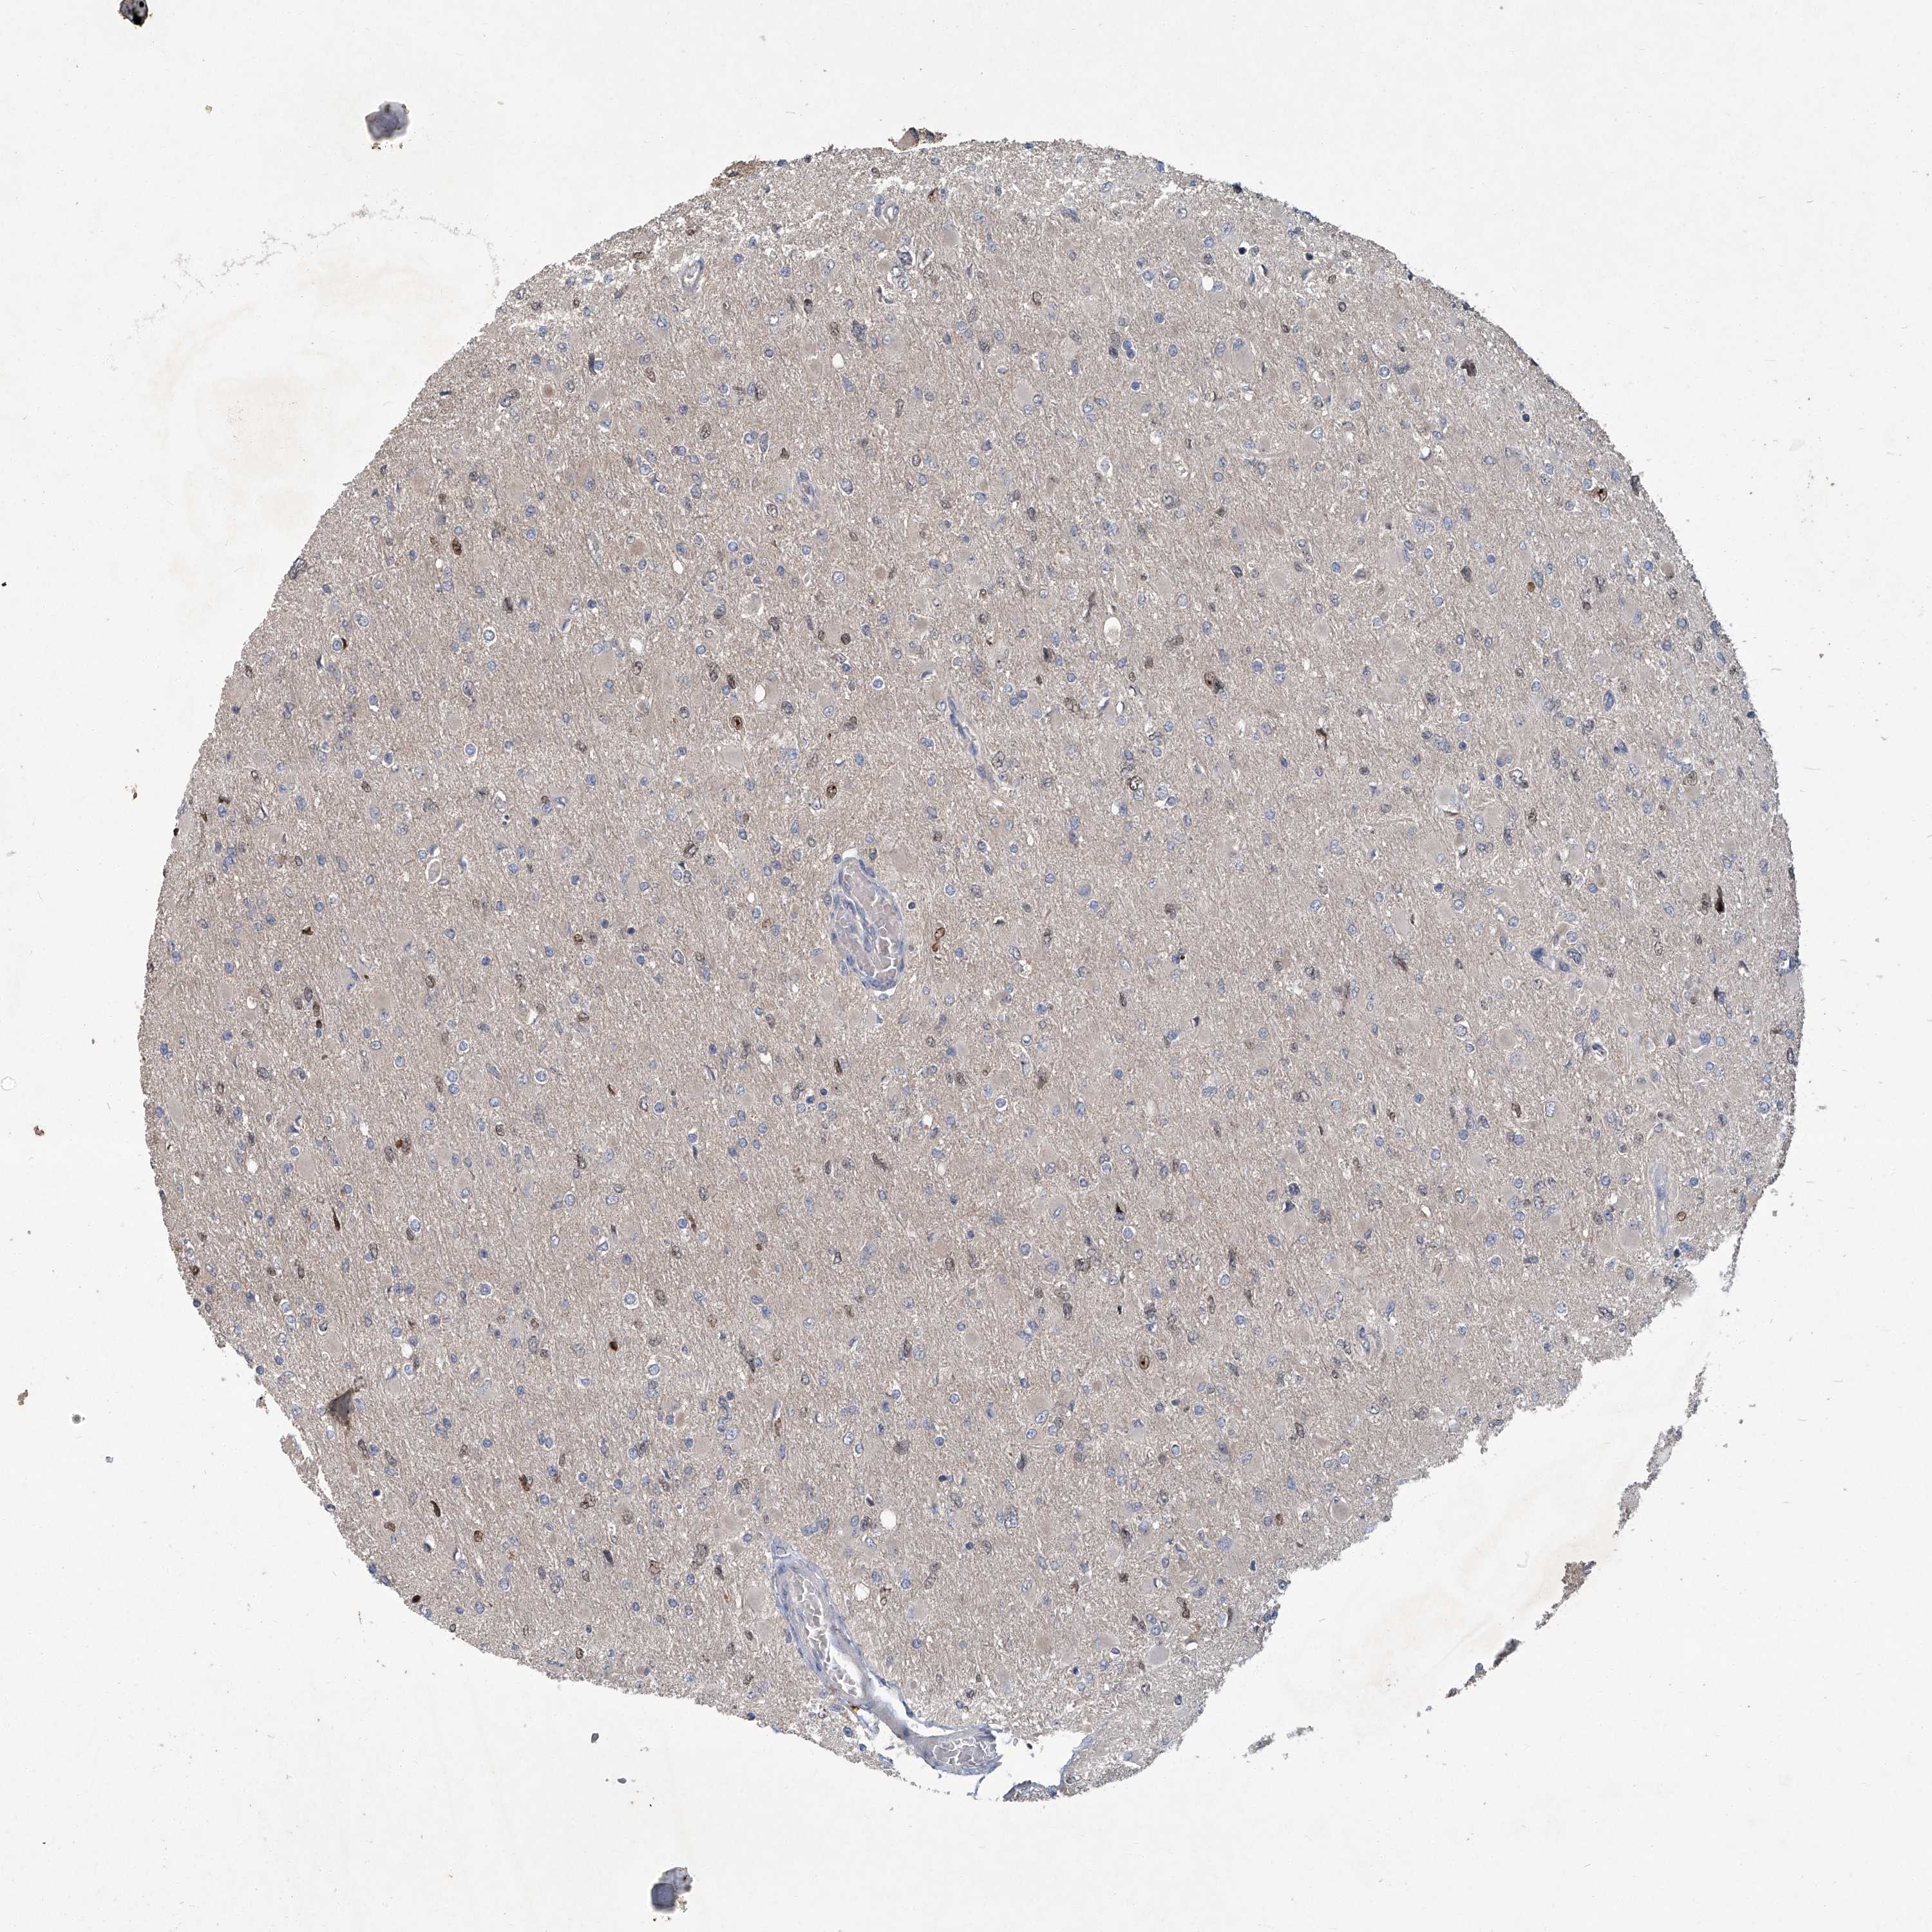

GLIOMA - Protein expressioni

A mouse-over function shows sample information and annotation data. Click on an image to view it in a full screen mode. Samples can be filtered based on level of antibody staining by selecting one or several of the following categories: high, medium, low and not detected. The assay and annotation is described here.

Note that samples used for immunohistochemistry by the Human Protein Atlas do not correspond to samples in the TCGA dataset.

Antibody stainingi

Antibody staining in the annotated cell types in the current human tissue is reported as not detected, low, medium, or high, based on conventional immunohistochemistry profiling in selected tissues. This score is based on the combination of the staining intensity and fraction of stained cells.

Each image is clickable and will lead to virtual microscopy that enables deeper exploration of all samples and also displays staining intensity scores, fraction scores and subcellular localization as well as patient and tissue information for each sample.

Antibody HPA029642

Antibody HPA029643

Glioma, malignant, High grade